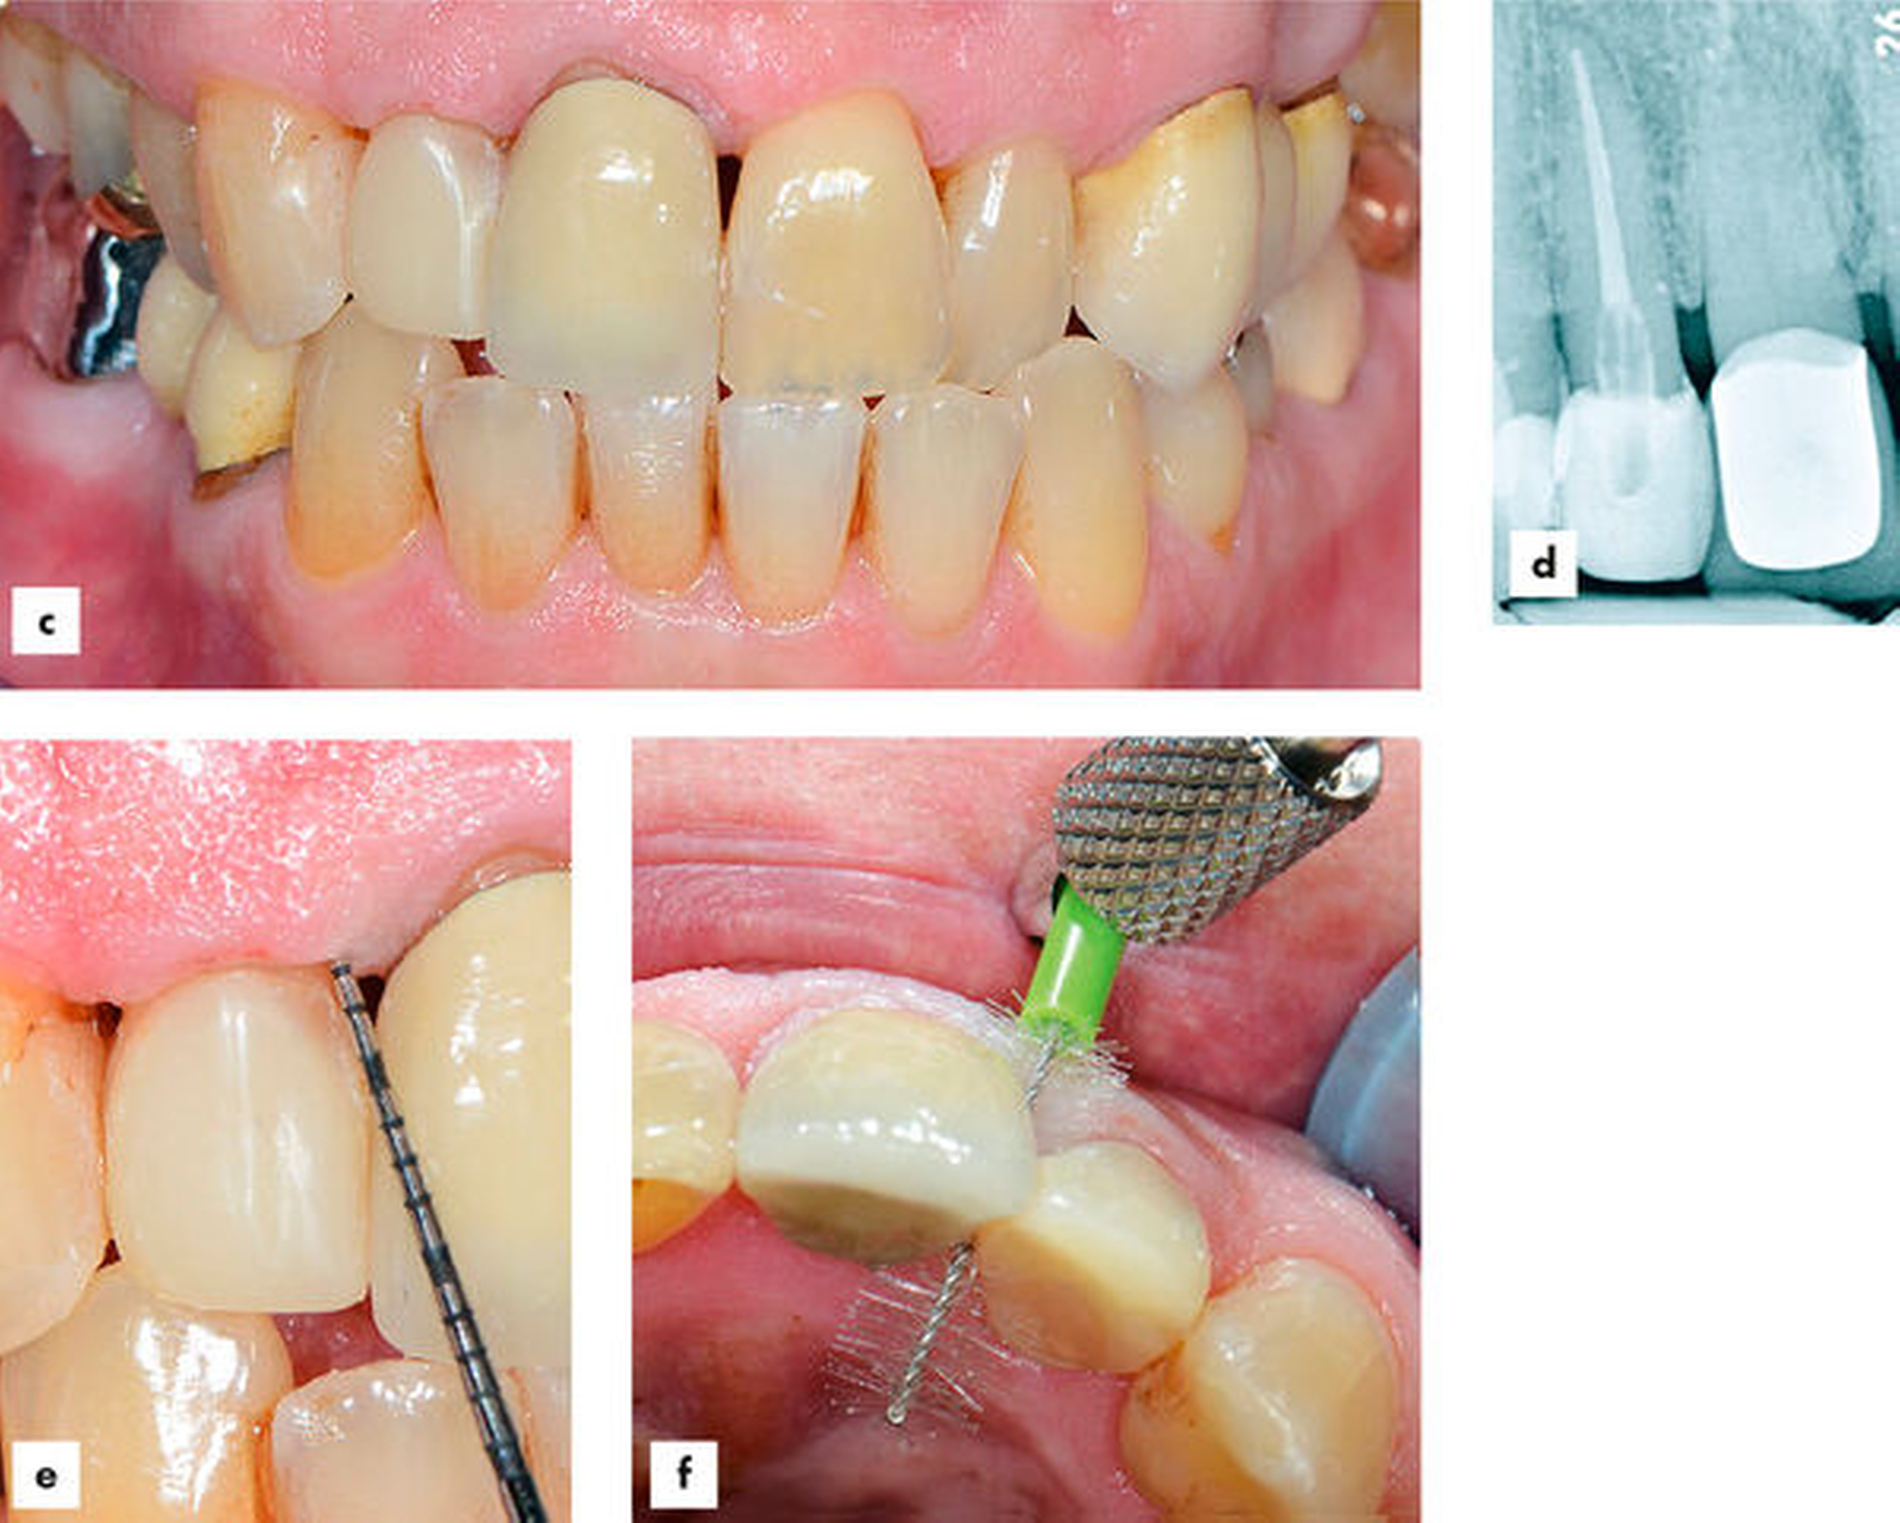

Ein 59-jähriger Mechaniker stellte sich mit frakturiertem Zahn 12 und verlorener Krone in der Poliklinik für Zahnerhaltungskunde der Klinik für Mund-, Zahn- und Kieferkrankheiten des Universitätsklinikums Heidelberg vor (Abbildungen 5a und 5b). Bei der Erhebung der allgemeinen Anamnese gab der Patient eine koronare Herzerkrankung und eine chronisch-obstruktive Lungenerkrankung (COPD) an. Er rauchte nicht, nahm ein Präparat zur Antikoagulation (Xarelto 10 mg) und bei Bedarf ein kortisonhaltiges Asthmaspray (Symbicort 160/4,5 µg/Dosis) ein. Zum Zeitpunkt der Erstvorstellung hatte der Patient keine Schmerzen, keine Zahnlockerungen und keine erhöhten Sondierungstiefen an Zahn 12. Da der Wurzelrest des Zahns 12 nach Verlust der Restauration umgehend mit provisorischem Zement abgedeckt worden war, konnte eine Reinfektion des Kanals nahezu ausgeschlossen werden. Der Röntgenbefund zeigte eine unauffällige periapikale Region und eine intraradikuläre Transluzenz im Sinne einer homogenen Wurzelkanalfüllung nach Restaurationsverlust, die bis etwa 1,0 mm vor das Foramen apikale reichte (Abbildung 5c).

Erste Phase: individueller Wurzelstift

Die wichtigsten für die R3-Technik verwendeten Materialien sind in Tabelle 2 aufgeführt.In der ersten Phase wurden die zugänglichen Oberflächen des Wurzelrests gereinigt, die Karies exkaviert und unter relativer Trockenlegung die Wurzelkanalfüllung um 5 mm gekürzt. Anschließend wurde das faserverstärkte Kompositmaterial, wie im vorherigen Fallbeispiel dargestellt, abgemessen (5 mm Wurzelkanal plus 5 mm koronaler Anteil) und mit einer Schere in der Verpackung zurechtgeschnitten. Nach Anätzen mit Phosphorsäure, Spülen und Trocknen von Wurzeloberfläche und Kanallumen des Zahns 12 erfolgte das Auftragen von Primer und Adhäsiv mit anschließender Lichthärtung. Daraufhin wurde zunächst eine kleine Menge eines fließfähigen Bulk-Fill-Komposits in den Wurzelkanal eingebracht. Im Anschluss wurde das faserverstärkte Kompositmaterial platziert und mit einer Polymerisationslampe mit speziellem Ansatz lichtgehärtet (Abbildungen 5d–5f). Aufgrund der Größe des Kanallumens wurde im vorliegenden Fall lediglich ein Strang des faserverstärkten Kompositmaterials eingebracht, bei großvolumigeren Kanälen hätten problemlos zwei bis drei Stränge fächerförmig in die Kompositmasse eingebracht und polymerisiert werden können.

Zweite Phase: Stumpfaufbau

In der zweiten Phase wurde zunächst zur Einstellung der korrekten Länge im koronalen Strumpfaufbau das faserverstärkte Kompositmaterial mit einem langsam rotierenden Diamanten ohne Wasserkühlung vorsichtig um circa 1,5 mm gekürzt (Abbildung 5g). Um die Sauerstoffinhibitionsschicht zu schützen und eine Kontamination mit Wasser zu vermeiden, wurde der Schleifstaub vorsichtig mit Luft entfernt. Anschließend wurde ein fließfähiges Bulk-Fill-Komposit um den faserverstärkten Kompositstrang herum im Sinne eines Stumpfaufbaus appliziert und lichtgehärtet (Abbildungen 5h–5j). Die aufgrund des Verzichts auf eine Matrize entstandenen marginalen Überhänge konnten mit einem feinkörnigen Separierdiamanten sowie einem sichelförmigen Skalpell (Nr. 12) gezielt entfernt werden.Da sich die Restauration im ästhetisch relevanten Frontzahnbereich befindet, war darauf zu achten, dass das fließfähige Bulk-Fill-Komposit eine passende Zahnfarbe aufweist. Universalfarben, die bei Bulk-Fill-Kompositen oftmals zur Anwendung im Seitenzahnbereich angeboten werden, hätten die direkte Kompositkrone möglicherweise etwas zu grau erscheinen lassen können. Die zweite Restaurationsphase der R3-Technik verfolgte das Ziel, einen zapfenartigen Stumpfaufbau mit einem vollständig bedeckten Kern aus faserverstärktem Kompositmaterial zu erhalten (Abbildung 5j).

Dritte Phase: direkte Kompositkrone

Die dritte Phase der R3-Technik beinhaltete die Herstellung einer direkten Kompositkrone am Frontzahn. Da nach Abschluss der zweiten Phase eine Art „Zapfenzahn“ als Ausgangssituation hergestellt worden war, konnten hier die Prinzipien zur Herstellung einer Zahnformkorrektur Anwendung finden, die hier jedoch nicht im Detail erläutert werden.

Zu Beginn wurde mit einer Schmelzmasse die palatinale Wand geschichtet (Abbildung 5k). Die Herstellung der palatinalen Wand kann nach vorherigem Wax-up am Modell mithilfe eines Silikonschlüssels erfolgen, alternativ kann die Kompositmasse wie in diesem Fall auch gegen den palatinal als Widerlager platzierten Finger des Behandlers geschichtet werden. Die approximalen Wände wurden mit der individuellen Matrizenverschalungstechnik nach Klaiber und Hugo mesial und distal aufgebaut [Klaiber, 2006] (Abbildung 5l). Nach dem Legen der Matrizen wurde zunächst etwas Flowkomposit in den Kontaktpunktbereich eingebracht, anschließend visköses Restaurationsmaterial darüber platziert und nach Verkeilen mit einem kleinen Heidemannspatel lichtgehärtet. Sobald die approximalen Wände aufgebaut waren, konnte der Dentinkern mit Charakterisierungen (Marmelons) geschichtet werden (Abbildung 5m). Zum Schluss wurde ein Überzug mit einer Schmelzmasse modelliert (Abbildung 5n).

Die Ausarbeitung der Kompositrestauration erfolgte nach den üblichen Kriterien. Eine Auswahl von passgenauen Interdentalraumbürstchen mit einer eingehenden Mundhygieneunterweisung fand zum Abschluss der Behandlungssitzung statt.

Nachkontrolle

Nach 16 Monaten zeigten sich klinisch entzündungsfreie und reizlose Verhältnisse (Abbildungen 6a–6f). Der Röntgenbefund offenbarte intrakanalikulär eine opake Struktur im Sinne des faserverstärkten Kompositmaterials. Hinweise auf periapikale Veränderungen waren nicht feststellbar (Abbildung 6d). Die Restauration präsentierte sich in einem funktionell und vom Aussehen her guten Zustand ohne jegliche Zeichen endodontischer oder parodontaler Irritationen (Abbildung 6e). Der Patient war zufrieden und nutzte täglich die individuell ausgewählte Interdentalraumbürste (Abbildung 6f).